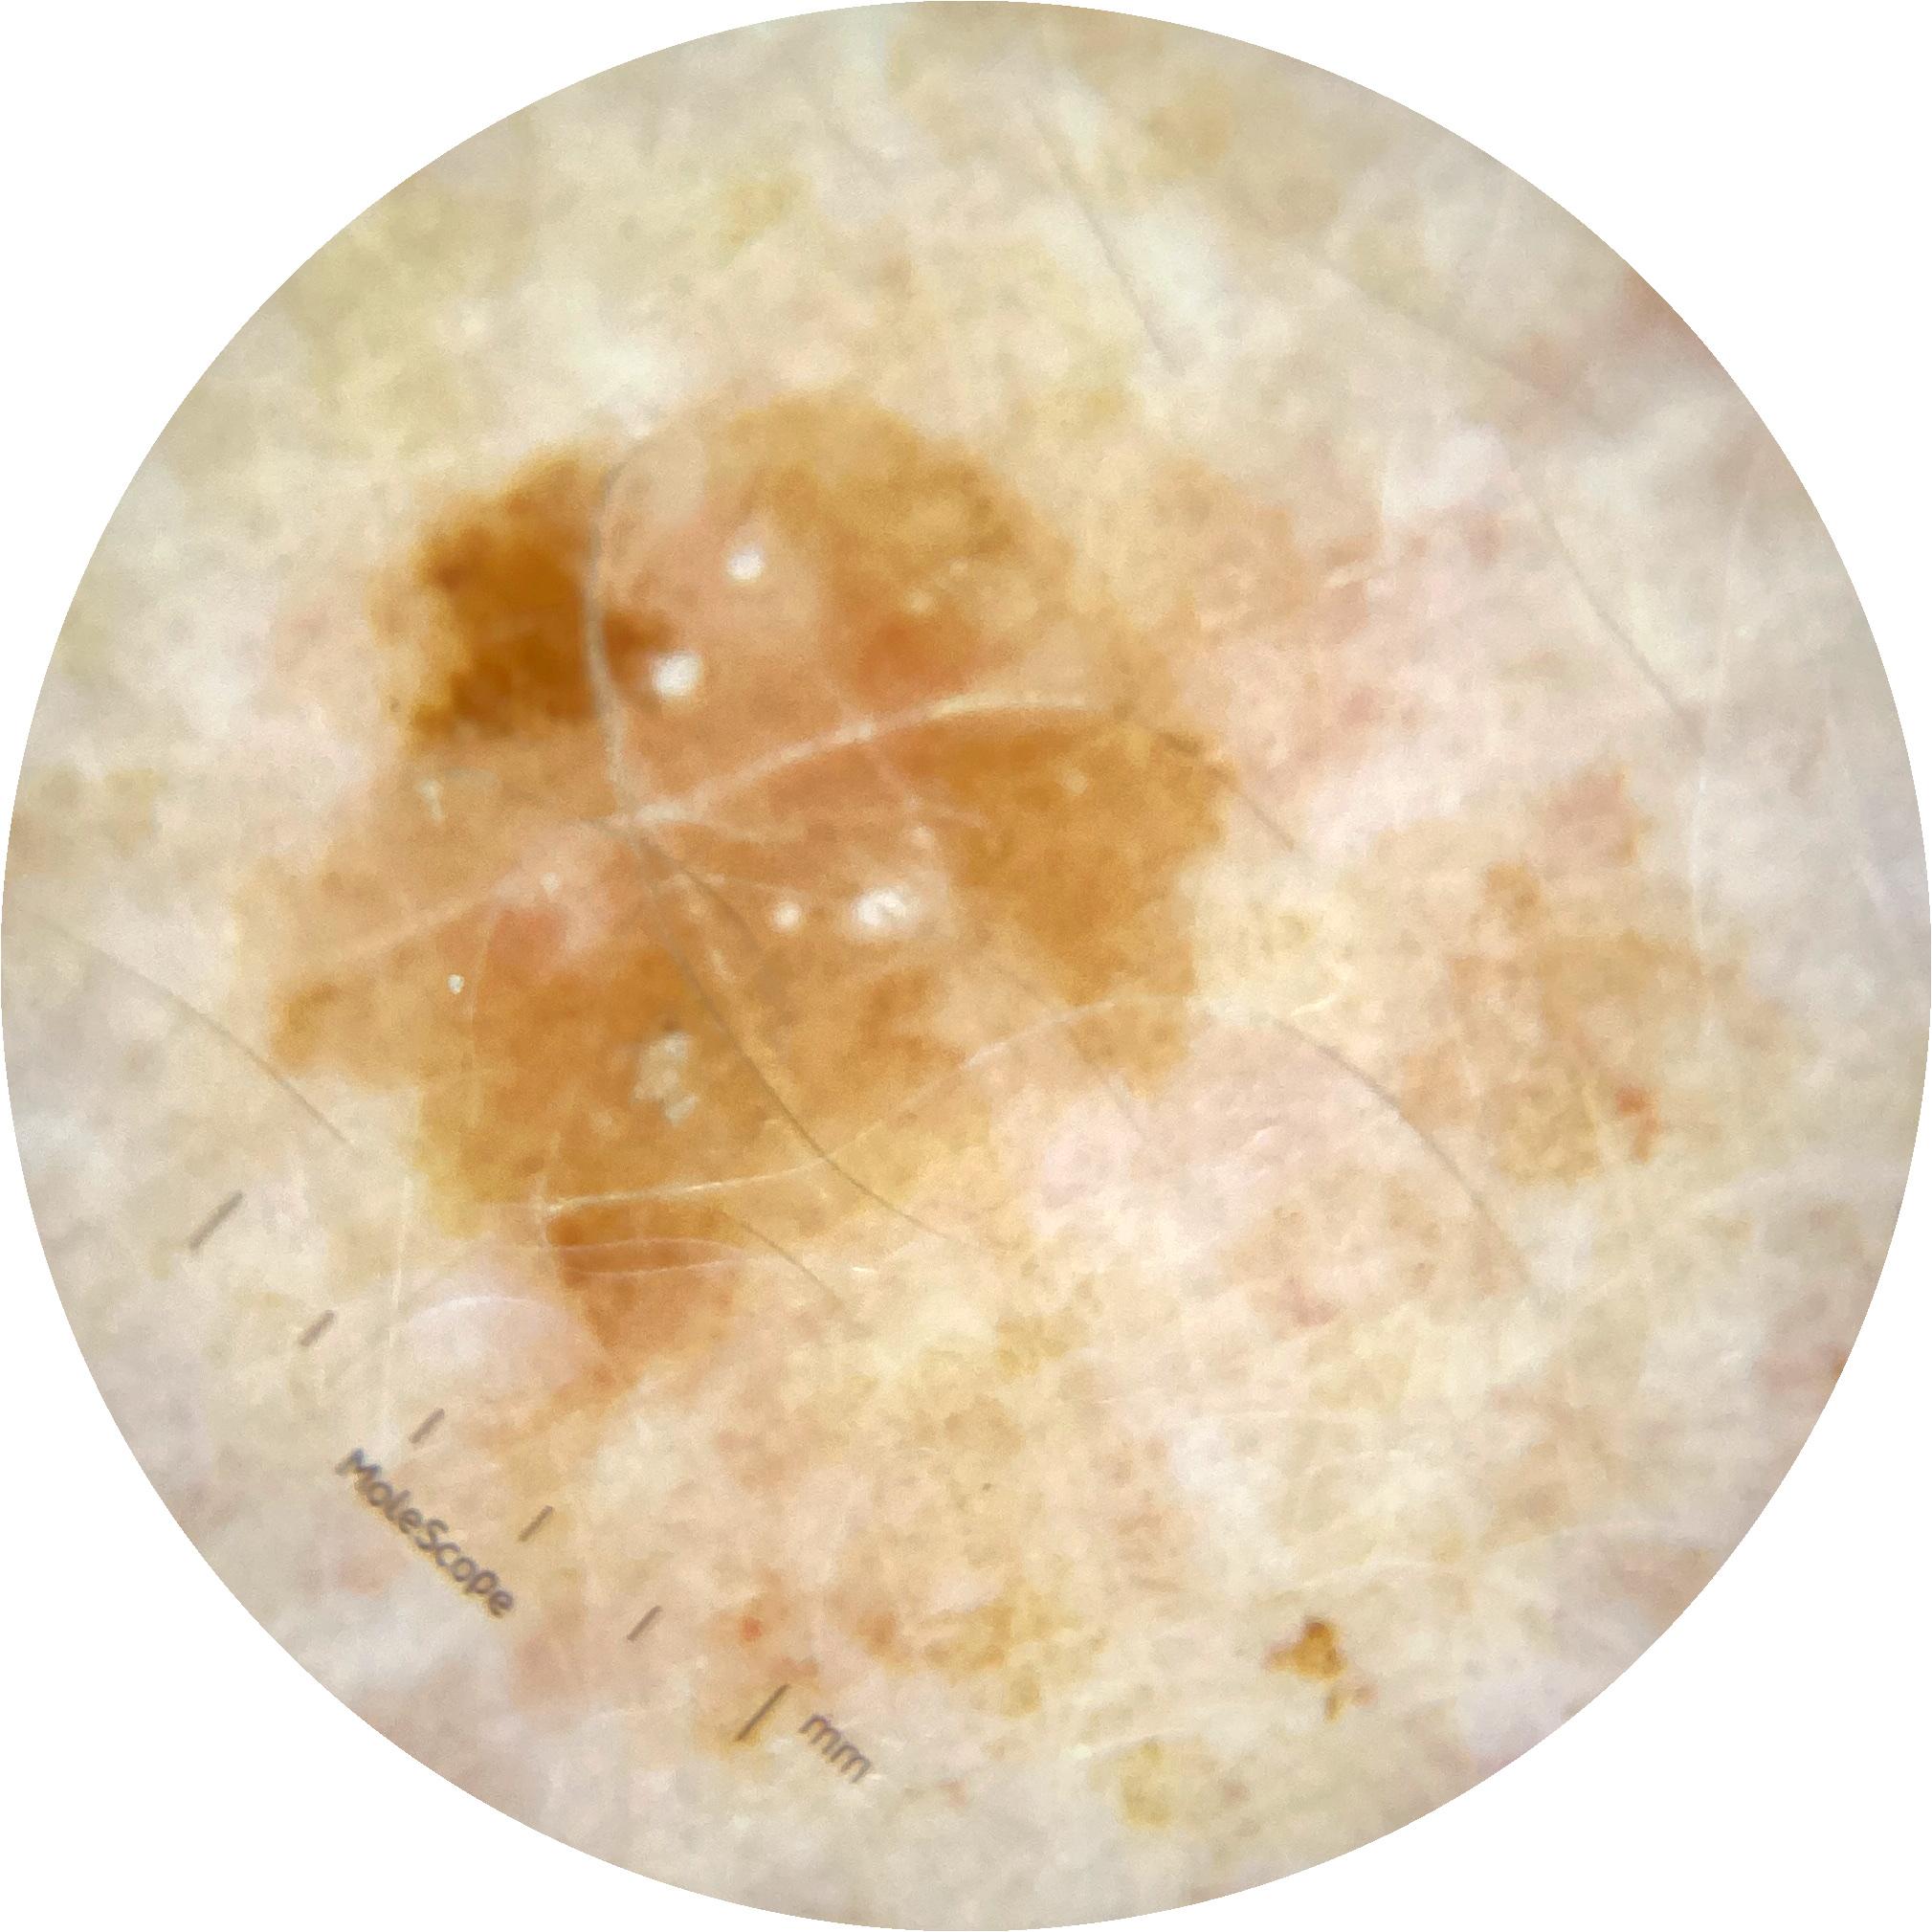

ISIC_8490164

2003 x 2003

MEL-SELF Trial, https://www.sydney.edu.au/medicine-health/our-research/research-centres/melself-project.html

acquisition_day 218

age_approx 65

anatom_site_1 Upper extremity

anatom_site_general upper extremity

diagnosis_1 Benign

diagnosis_confirm_type single image expert consensus

fitzpatrick_skin_type I

image_type dermoscopic